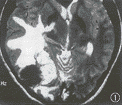

图1 T2WI示病灶呈混杂信号,有大的血管流空影,瘤周水肿明显

图2 MRI增强扫描示病灶位于右枕部,边界清晰,边缘不规则,呈不均匀明显强化

术前CT和 MRI扫描对颅内血管外膜细胞瘤和脑膜瘤难以作出明确鉴别,但脑血管造影在这一方面却有较大意义[4,5]。CT平扫肿瘤呈略高密度,边界多较清晰,呈不规则分叶状,瘤内低密度的囊性变或坏死多见,肿瘤附近骨质一般无反应性增生,且可发生局限性溶骨破坏,病灶内部钙化少见,这不同于一般脑膜瘤[5]。血管外膜细胞瘤的 MRI信号变化很复杂,T1WI上病灶呈等或低等混杂信号;T2WI上呈等或略低信号,且随回波时间延长信号有衰减,但也可表现为高信号,瘤周水肿多较明显,常见血管流空影,呈不均匀明显强化(图1,2)。血管造影可见肿瘤染色明显,瘤内血管为不规则排列,不同于脑膜瘤血管均匀排列,有的呈血管畸形样表现(图3)。